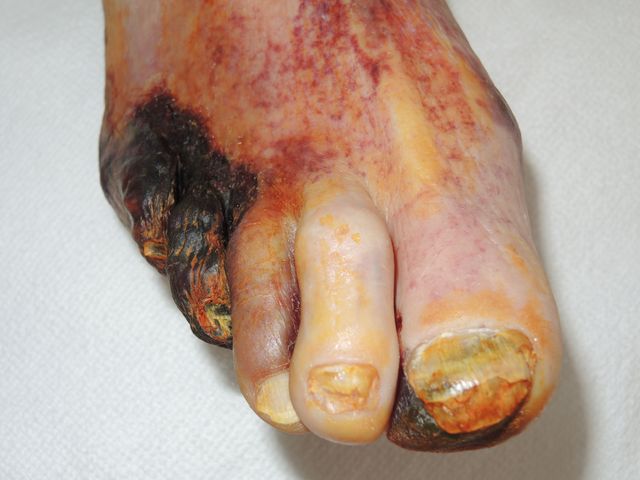

Necrosis periférica en pie diabético.